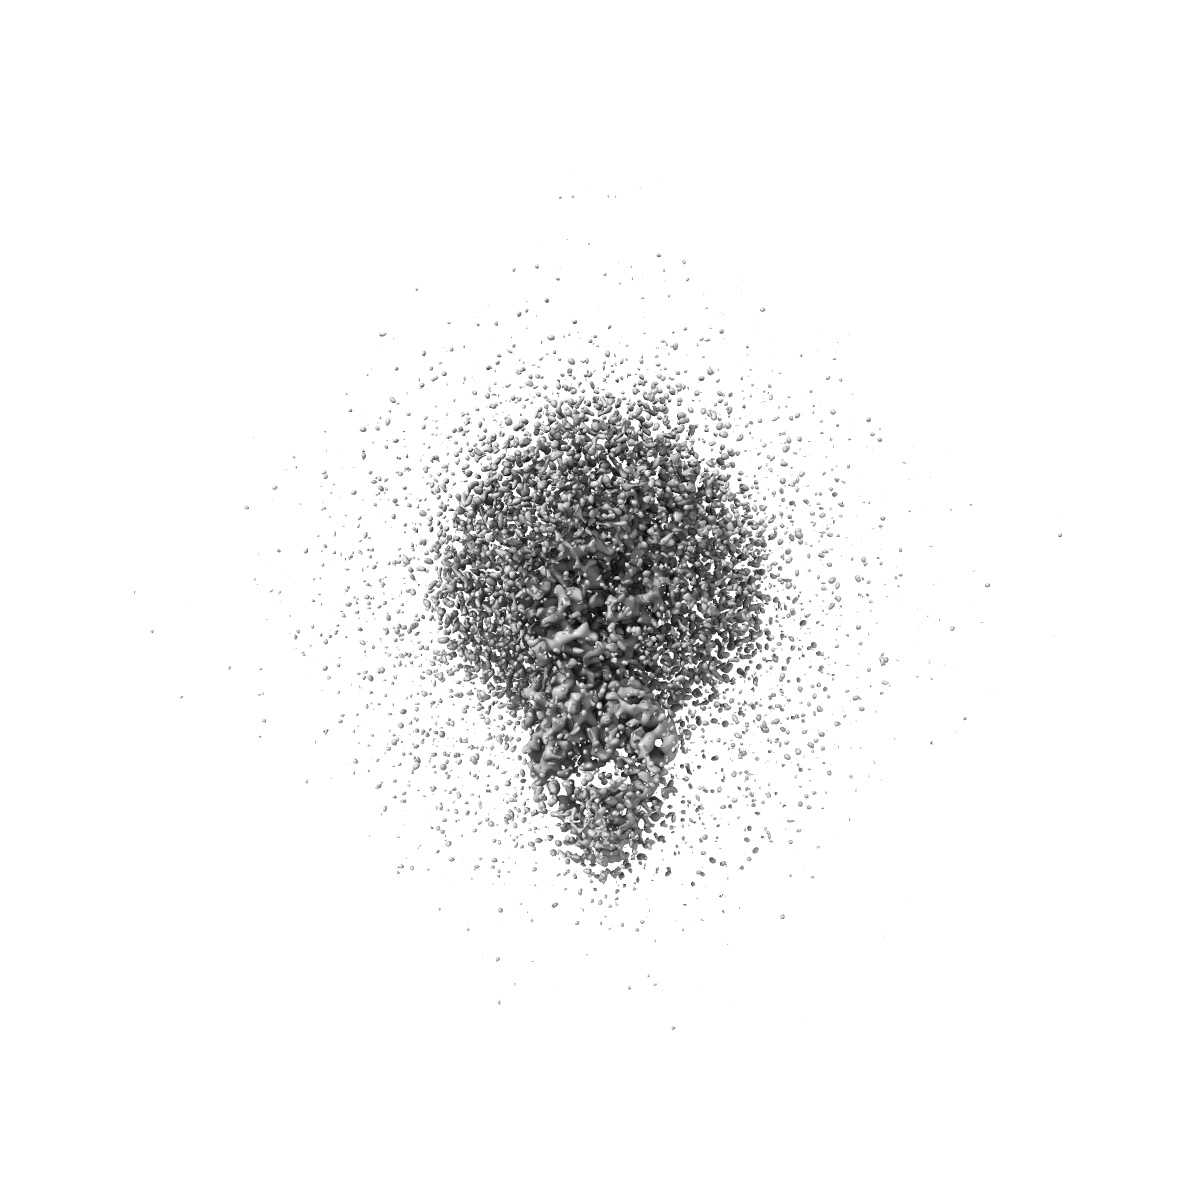

Cryo-EM Structure of the wild-type human serotonin transporter in complex with ibogaine and 15B8 Fab in the inward conformation

Sample Organism: Mus musculus, Homo sapiens

Sample: Human serotonin transporter in complex with Fab bound to ibogaine

Fitted models: 6dzz

Serotonin transporter-ibogaine complexes illuminate mechanisms of inhibition and transport.

Coleman JA, Yang D, Zhao Z , Wen PC , Yoshioka C, Tajkhorshid E, Gouaux E

(2019) Nature , 569 , 141 - 145